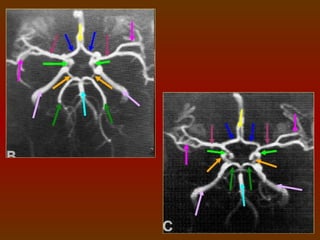

CÍRCULO OU POLÍGONO DE WILLIS

É um círculo de artérias que suprem o cérebro. Foi nomeado em

homenagem a Thomas Willis (1621 – 1873), médico inglês.

A. Cerebral

A. Comunicante

Anterior Direita

Anterior

A. Carótida

Interna Direita                               A. Cerebral Anterior

Esquerda

Média                                     A. Carótida Interna

Posterior Direita                               A. Comunicante

Posterior Esquerda

Posterior Direita                                 A. Cerebral

A. Basilar

CIRCULAÇÃO SANGUÍNEA DO CÉREBRO

O sangue chega ao cérebro através das artérias vertebrais e

das artérias carótidas internas, que se comunicam através do

polígono de Willis, este é uma anastomose arterial que fornece o

suprimento sangüíneo para os hemisférios cerebrais, sendo

formado pelas artérias cerebrais anteriores e posteriores, artérias

comunicantes anterior e posteriores e pela carótida interna.

COMPONENTES

 Artéria cerebral anterior (direita e esquerda).

 Artéria comunicante anterior.

 Artéria carótida interna (direita e esquerda).

 Artéria cerebral posterior (direita e esquerda).

 Artéria comunicante posterior (direita e esquerda).

IMPORTÂNCIA FISIOLÓGICA

O arranjo das artérias no

Polígono   de    Willis    cria uma

redundância na circulação cerebral.

Se uma parte do círculo estiver

bloqueada ou estreitada (estenose),

ou se uma das artérias que suprem o

polígono    está     estreitada  ou

bloqueada, o fluxo sanguíneo dos

outros vasos sanguíneos podem

muitas vezes preservar a perfusão

cerebral .

ESTUDO DO POLÍGONO DE WILLIS

 1 mm espessa X 1 mm incremento.

 Em média 100 ml de contraste, a 3ml/s.

A marcação vai da

base do seio

esfenoidal ao topo

do corpo caloso.